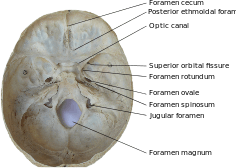

Image of base of the skull with several of the foramina labeled.

The human skull has numerous holes (foramina) through which cranial nerves, arteries, veins and other structures pass.